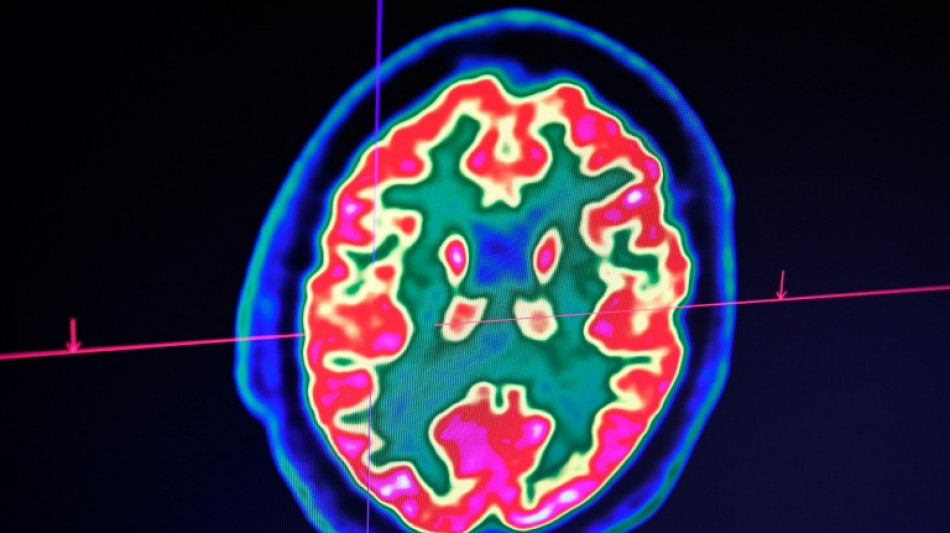

D'emblée, Lucas répond très bien au traitement. "Au fil des IRM, j'ai vu la tumeur complètement disparaître", raconte le Dr Grill, qui n'ose, malgré ces résultats miraculeux, décider d'arrêter le médicament. Jusqu'à ce qu'il comprenne, il y a un an et demi, que l'enfant avait lui-même cessé de le prendre.